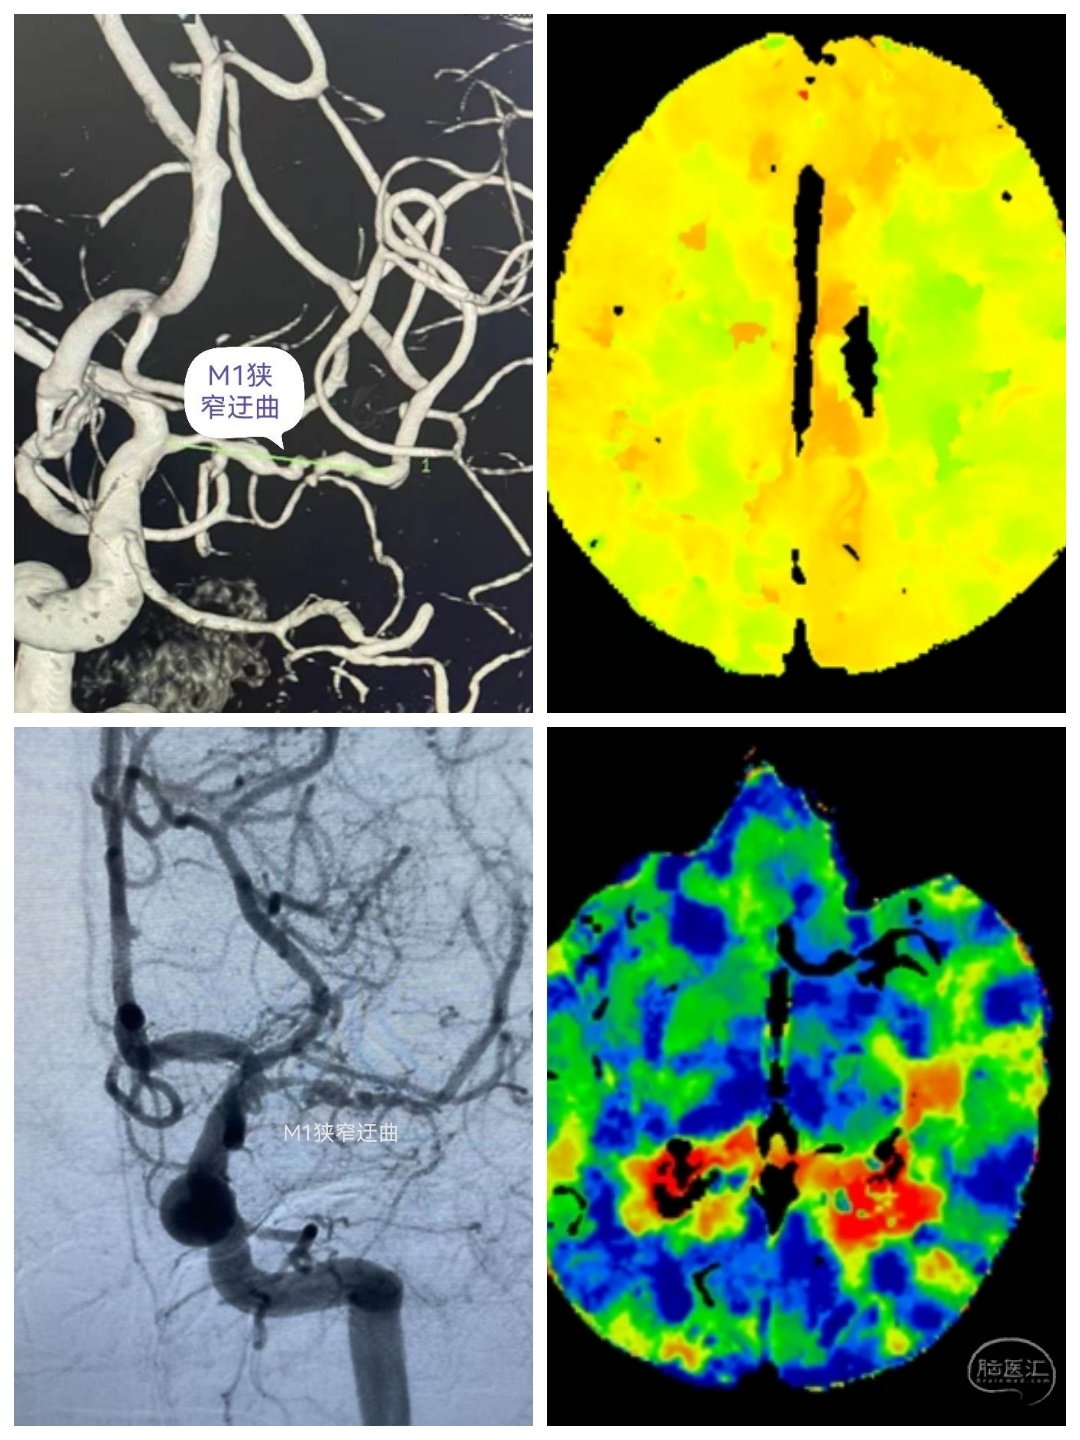

张某,男性,72岁,因“右侧肢体乏力不适三个月”入院。

CT及CTA提示左侧大脑灌注不足,左侧大脑中动脉M1狭窄。考虑此处串通支较多,予以搭桥手术。

术中游离颞浅动脉,暴露大脑中动脉M4段,行STA-MCA吻合术。

半年后患者来我科复查DSA。颞浅动脉与M4血管吻合满意,颈外动脉造影可见大脑中动脉显影,天堑造通途。。。